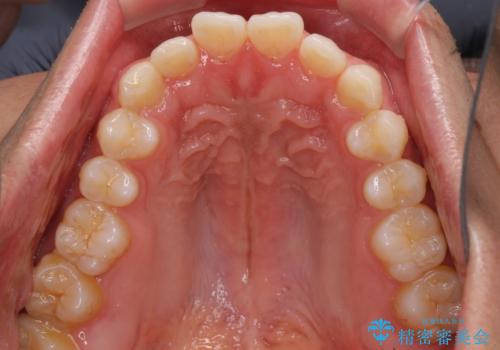

細かい隙間にものがはさまる インビザラインによる矯正治療

- 上下の前歯の隙間を気にして来院された患者様です。

インビザラインを用い、上下歯列のスペースを閉じていくこととしました。